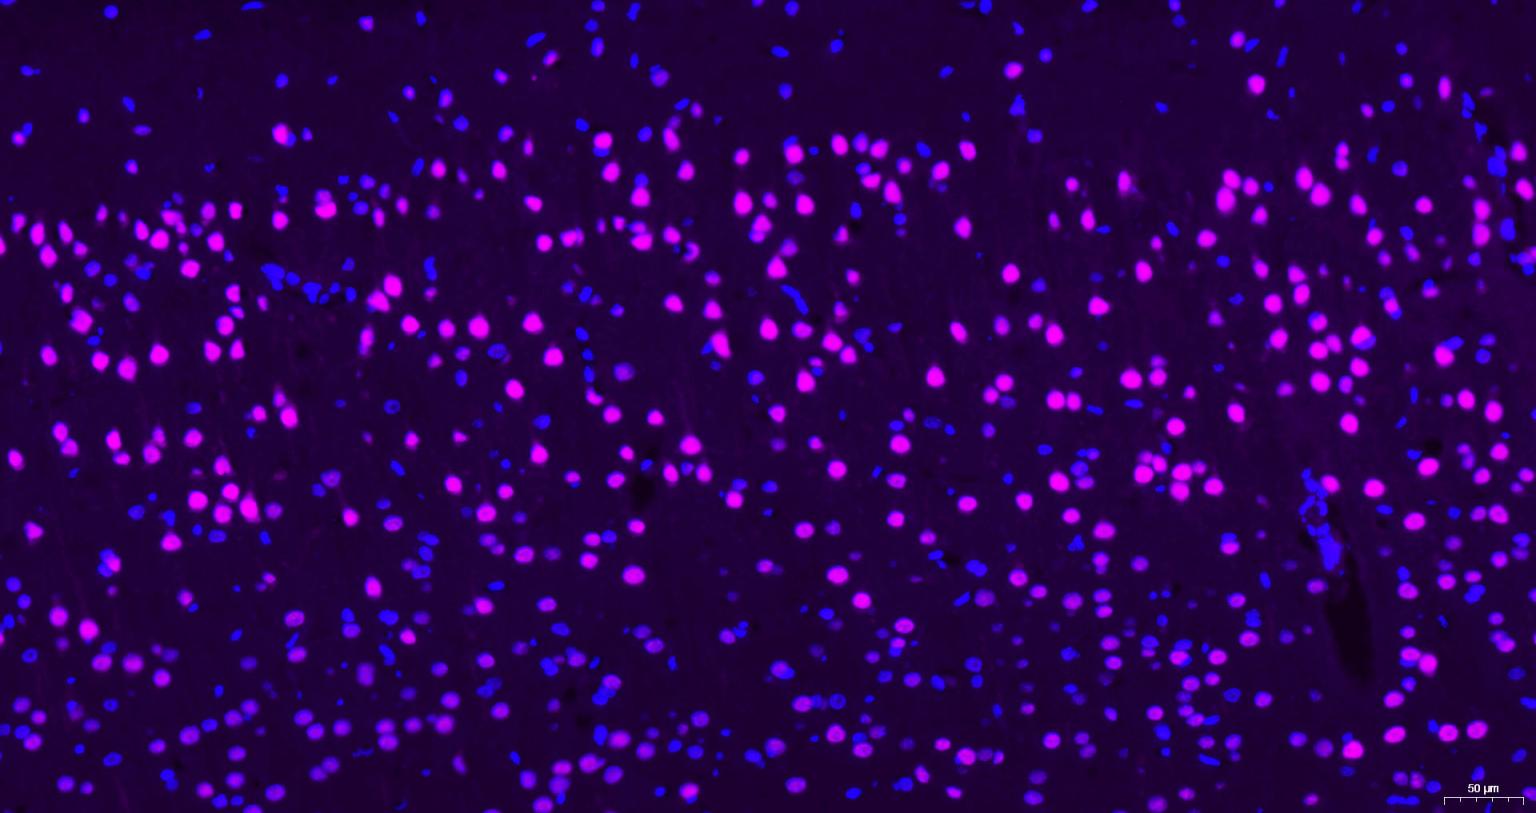

Paraformaldehyde-fixed, paraffin embedded Human brain; Antigen retrieval by boiling in sodium citrate buffer (pH6.0) for 15 min; Antibody incubation with AKT1 Monoclonal Antibody, Unconjugated(bsm-52010R) at 1:200 overnight at 4°C, followed by a Cy5 conjugated Goat Anti-Rabbit IgG (bs-0295G-Cy5)antibody at 37°C for 90 minutes, DAPI (blue, C02-04002) was used to stain the cell nuclei.

Paraformaldehyde-fixed, paraffin embedded Mouse brain; Antigen retrieval by boiling in sodium citrate buffer (pH6.0) for 15 min; Antibody incubation with AKT1 Monoclonal Antibody, Unconjugated(bsm-52010R) at 1:200 overnight at 4°C, followed by a Cy5 conjugated Goat Anti-Rabbit IgG (bs-0295G-Cy5)antibody at 37°C for 90 minutes, DAPI (blue, C02-04002) was used to stain the cell nuclei.

Paraformaldehyde-fixed, paraffin embedded Rat brain; Antigen retrieval by boiling in sodium citrate buffer (pH6.0) for 15 min; Antibody incubation with AKT1 Monoclonal Antibody, Unconjugated(bsm-52010R) at 1:200 overnight at 4°C, followed by a Cy5 conjugated Goat Anti-Rabbit IgG (bs-0295G-Cy5)antibody at 37°C for 90 minutes, DAPI (blue, C02-04002) was used to stain the cell nuclei.